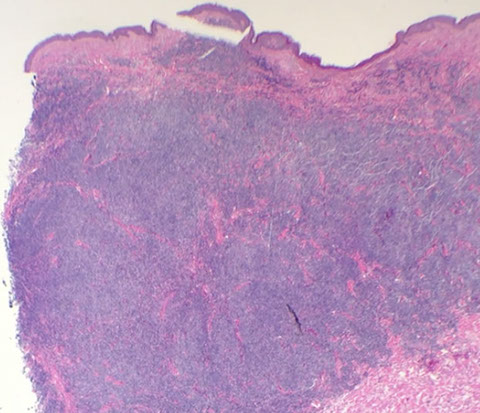

Cutaneous lymphoid hyperplasia in a 72-year-old man who presented with several purple-brown plaques on his cheeks and temples. A, The nodular infiltrate extends through the dermis with sparring of the overlying epidermis. B, It is characterized by scattered follicles with well-defined, reactive-appearing germinal centers, some of which have surrounding mantle zones. Many CD20-positive B cells are in the reactive follicles (C), and more numerous CD3-positive small T cells are present in the interfollicular areas (D). B-cell clonality studies (not shown) were negative for a clonal IGH or IGK gene rearrangement. [19]